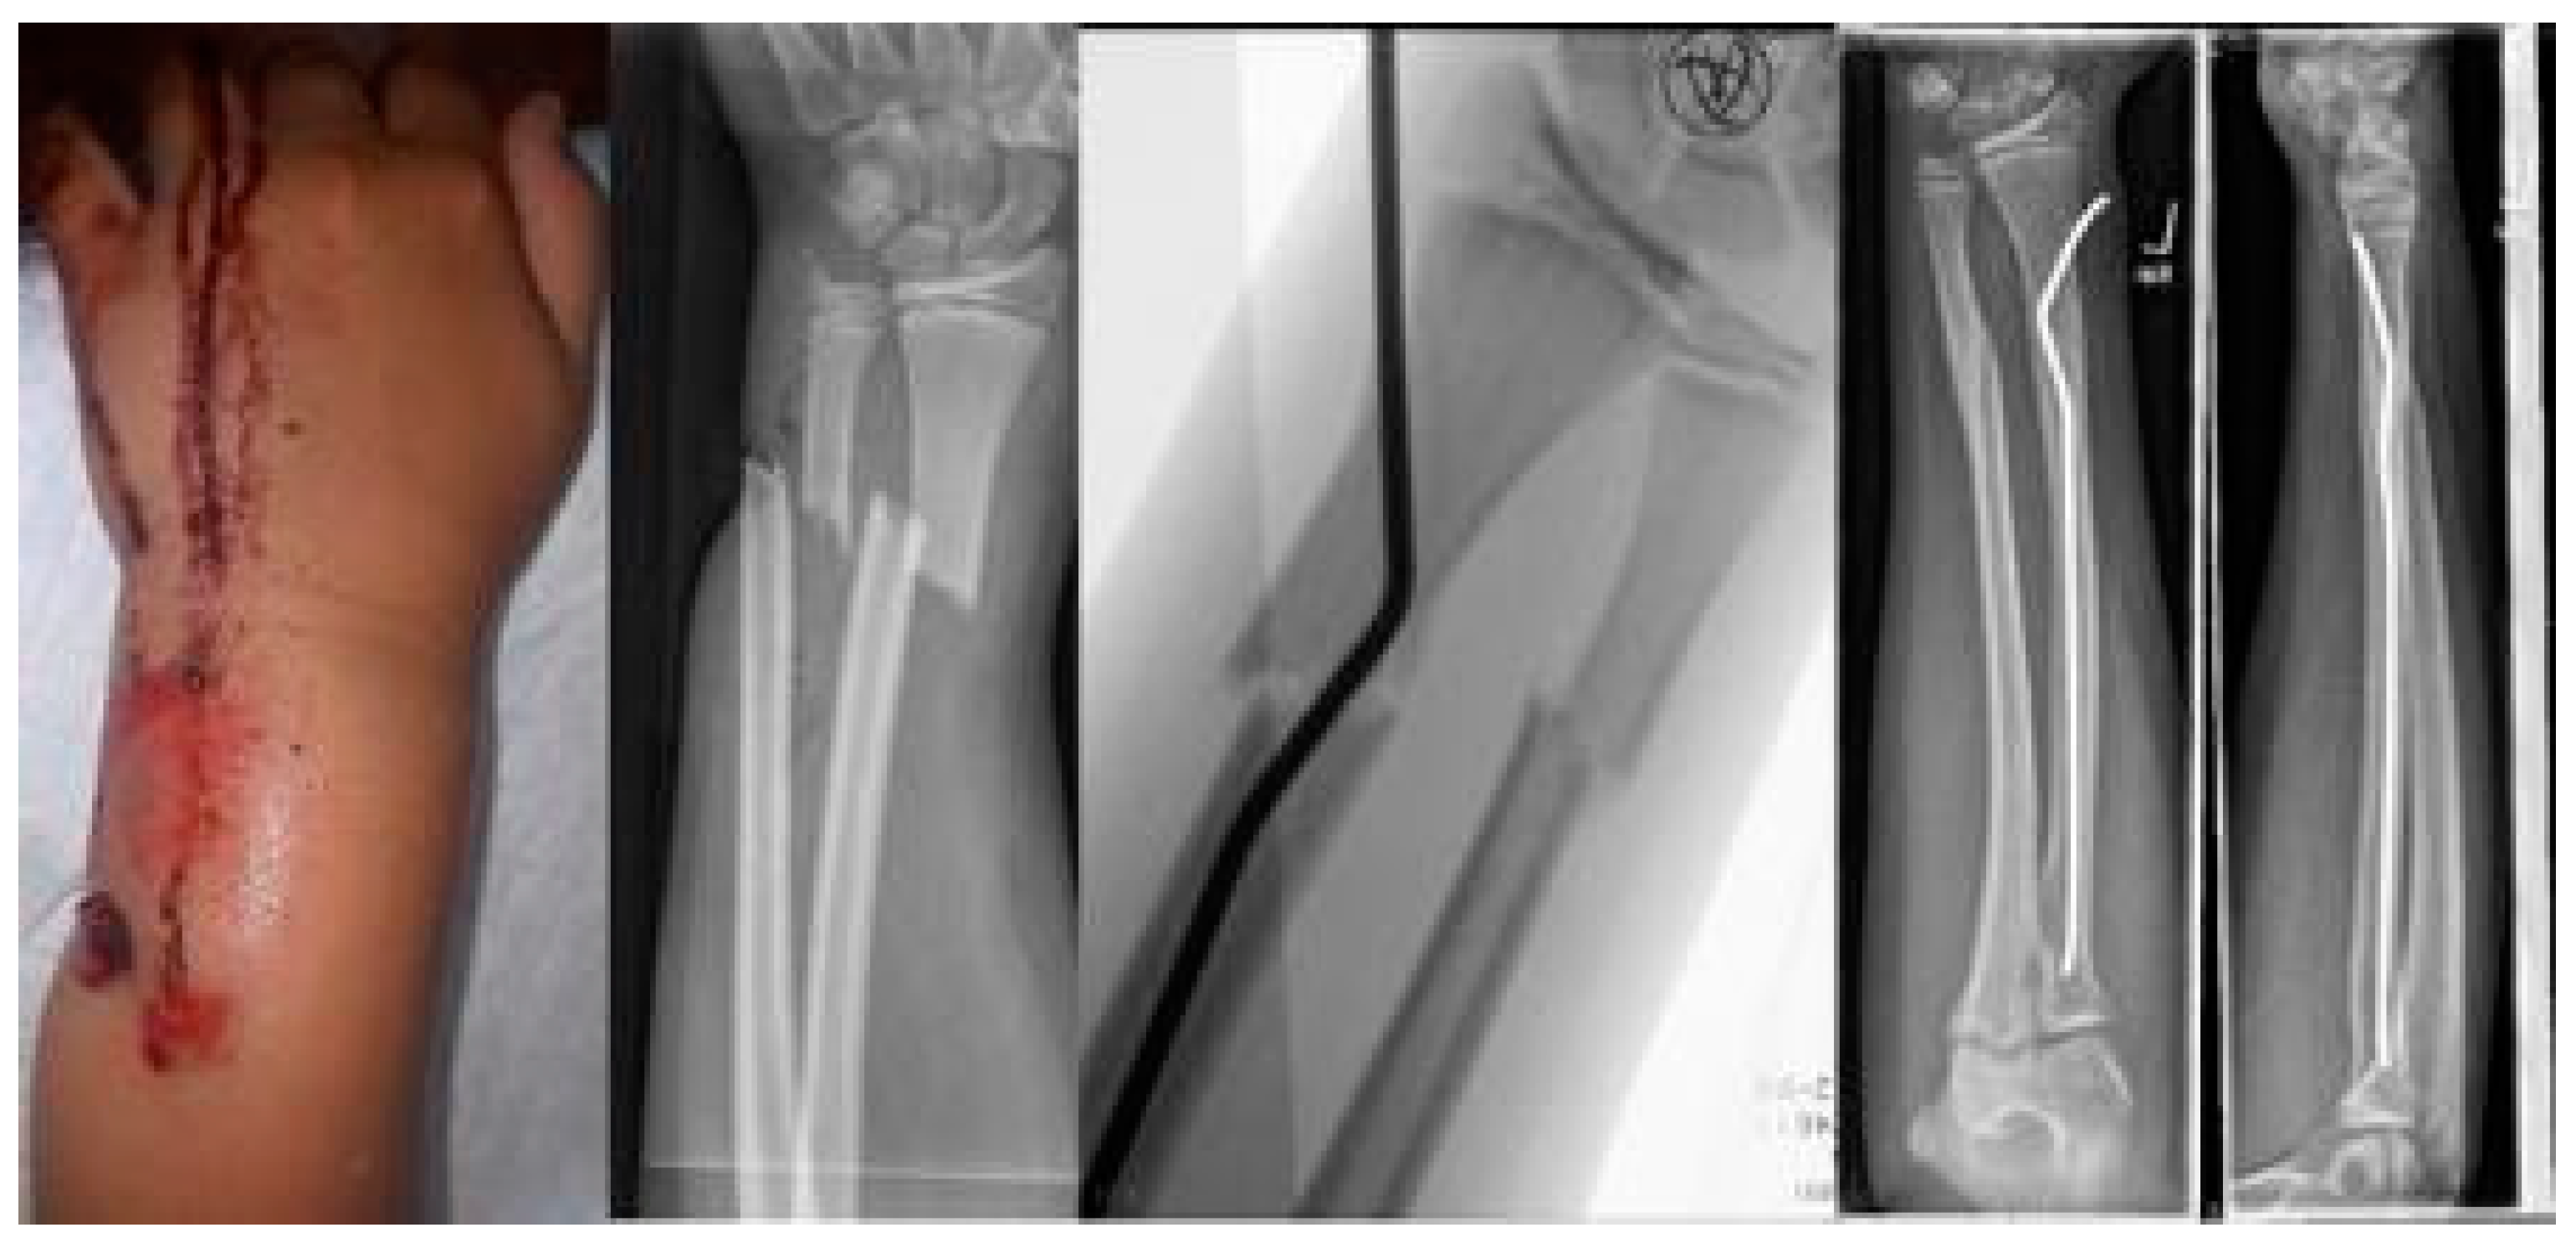

The youngest patient was a two-year old boy, who presented with an unacceptable secondary displacement two weeks after trauma and, thus, this fracture became a rare indication for osteosynthesis in this age group (Scheme 2). The eldest was 17 years of age and did not show epiphyseal plates anymore (Scheme 3). This patient, however, suffered a new trauma 3 weeks later and underwent a redo-procedure in another hospital and, thus, was lost to follow-up. We even treated an open forearm fracture (on the ulnar side) with this technique (Scheme 4), leaving the fracture of the ulna to spontaneous healing and correction. This was because the risk of osteomyelitis due to intramedullary nailing of the open ulnar fracture to achieve a “nice X-ray” was estimated to be much higher than the risk of a remaining misalignment. Even a redo-procedure of a fracture that we had seen for the first time 4 weeks after an unacceptable K-wire osteosynthesis was successful, this time using a modification of the technique with a bend, rather than a kink distal to the fracture. Please note that the pre-bent nail pushed the 4-week-old fracture into a correct position without open reduction (Scheme 4). Last but not least, curiously, we saw one patient who suffered identical fractures in both arms, so we could perform the procedure twice in one operation (Scheme 5).

Scheme 1. Closed reduction 4 weeks after insufficient k-wire osteosynthesis with a bend instead of the distal kink as a variant of this procedure.

Scheme 4. Open forearm fracture leaving the fracture of the ulna to spontaneous correction.